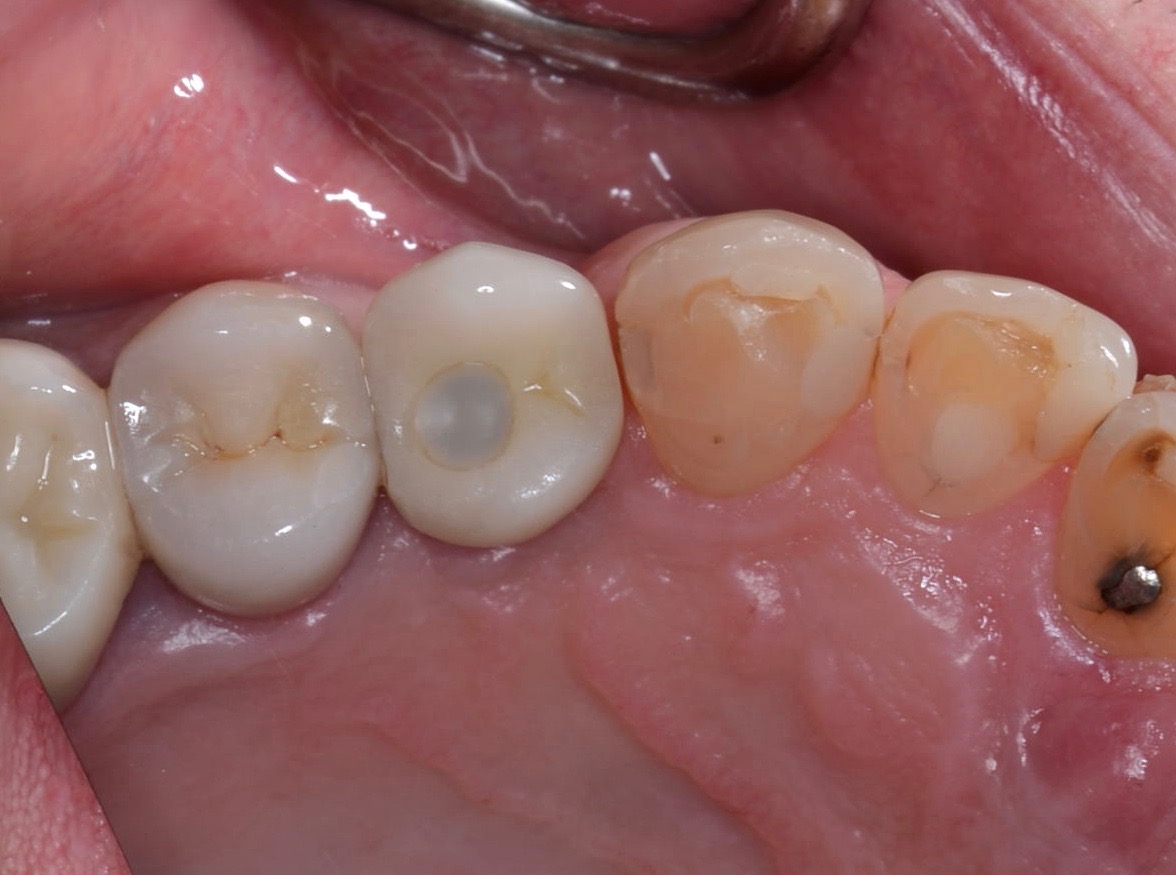

Fig 8. Loss of restoration and subsequent tissue overgrowth from broken abutment screw as shown in the radiograph (Fig 9).

Figure 8